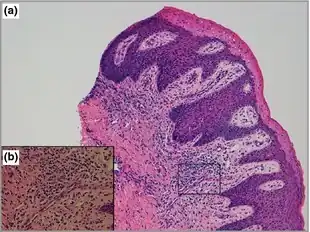

- I - Ichthyosiform Erythroderma—At birth or shortly after birth, there are red, inflamed patches (erythroderma), and flaky scales (ichthyosis) on the side of the body that is affected. Hair loss on the same side may also be possible.

The symptoms would appear at birth or shortly after birth. The combination of physical symptoms on the child would suggest they have CHILD syndrome. A skin sample examined under a microscope would suggest the characteristics of the syndrome and an X-ray of the trunk, arms, and legs would help to detect underdeveloped bones. A CT scan would help detect problems of the internal organs.